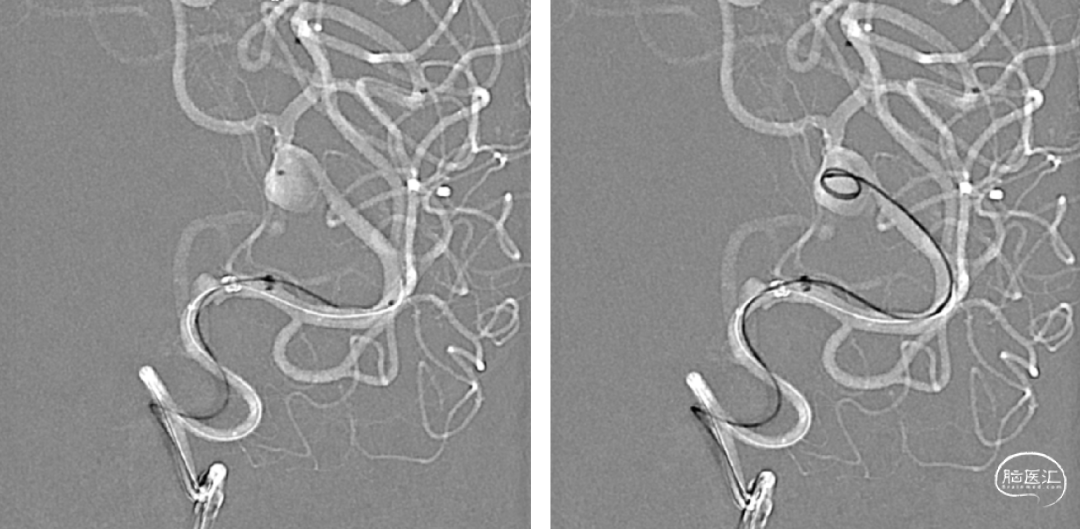

手术规划:FD+弹簧圈

FRED 3.0x14/19